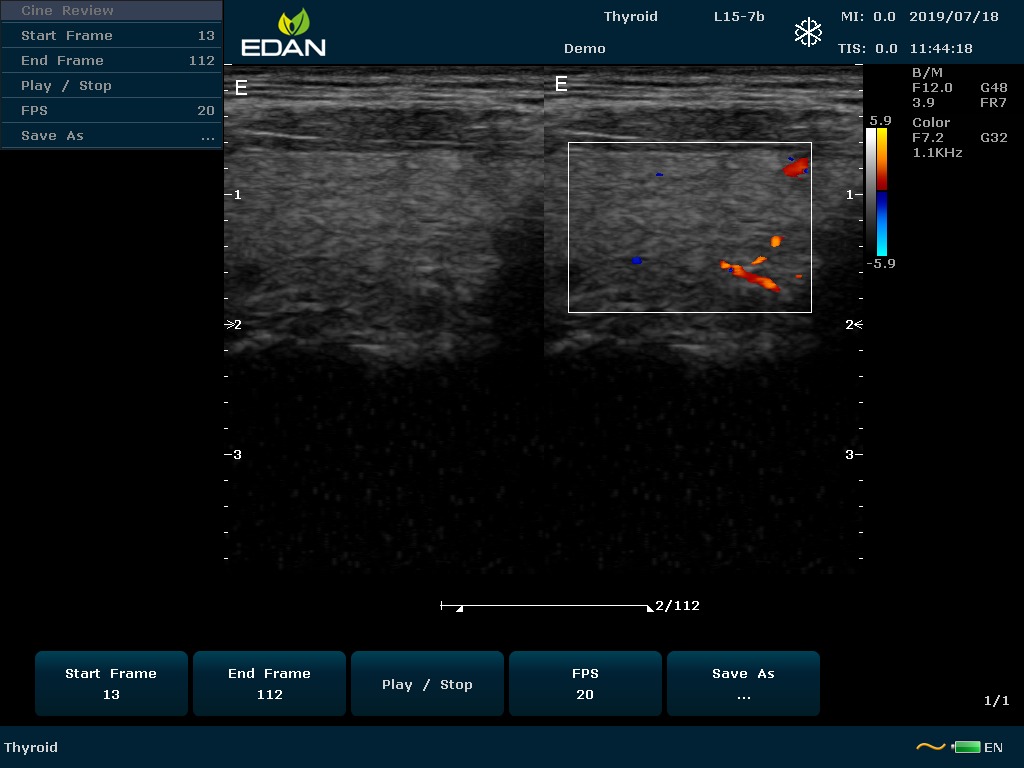

Особенность U60 Edan — расширенное применение. Ультразвуковой аппарат рекомендован для абдоминальных исследований, гинекологии и акушерства, кардиологии, педиатрии, урологии, изучения малых органов, сосудов. Для U60 Edan используются конвексные, линейные, фазированные и внутриполостные датчики.

Передовые технологии позволяют повысить качество визуализации в несколько раз. УЗИ-аппарат U60 Edan отличается возможностью быстрой настройки визуализации. Специальные функции позволяют моментально отображать данные за счет быстрой оптимизации параметров. Режимы визуализации: B-mode, M-mode, Color Doppler, Power Doppler Imaging, Pulsed Wave Doppler, Continuous Doppler.

• Цветовое Допплеровское картирование